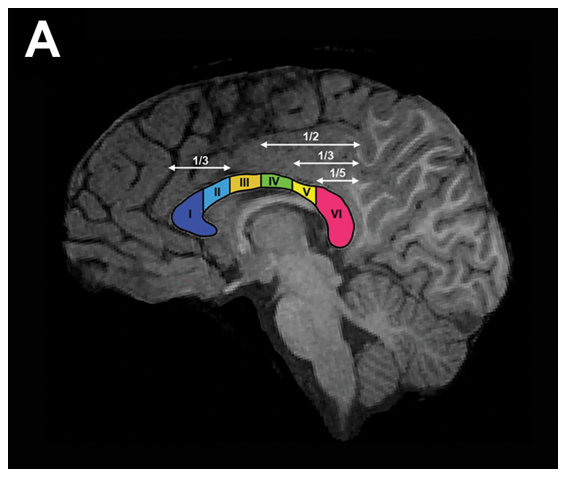

Штучний інтелект нагадав мені що, міст між правою та лівою півкулею називається corpus callosum.

Не знаю чи доречно буде додавати, що corpus callosum має три відділи : передній відділ, тіло та

задній відділ (A,B,P)